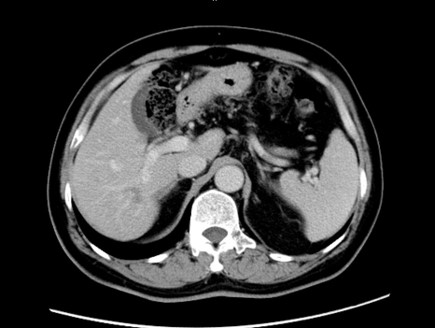

腹盆腔增强CT:肝脏多发低密度灶,转移瘤可能性大;乙状结肠占位。

腹部增强CT:

2014-9-19(化疗前):

2014-11-18(2cs化疗后):

2015-1-6(4cs化疗后):

2015-2-28 (6cs化疗后):